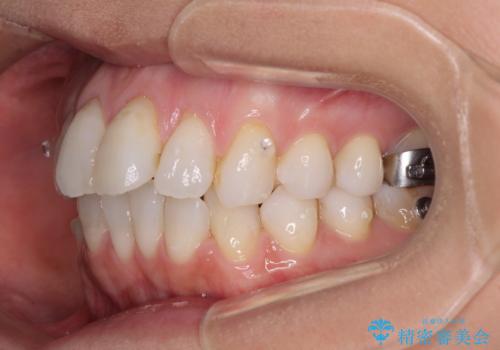

上顎歯列全体を後方に移動させる必要があり、インビザライン単体での治療は困難と判断し、補助装置により左右側方歯列を移動させた後にインビザラインを用いることとしました。

インビザライン単独でも上顎歯列全体を後方移動することで臼歯の咬み合わせを改善できる場合もあります。しかしながら、矯正治療は当初設定したゴールに到達する必要があり、今回のような場合ではインビザライン単独では達成の可能性が低くなるので、補助装置を使用して、より確実に治療を行うこととしています。